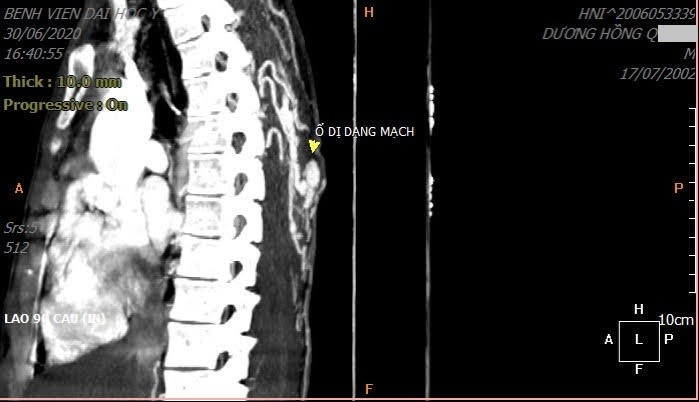

Bác sĩ phát hiện bệnh nhân có một khối dị dạng mạch rất lớn ẩn dưới vết chảy máu ngoài da. Búi thông động tĩnh mạch lan tỏa dưới da và trong cơ lưng cùng động mạch đi vào ổ dị dạng, tách trực tiếp từ động mạch chủ ngực. Áp lực dòng chảy lớn, phần nằm nông dưới da của ổ dị dạng to dần theo thời gian, khi vỡ gây chảy nhiều máu, nếu không được cầm máu kịp thời sẽ ảnh hưởng tính mạng.

Bác sĩ Nguyễn Ngọc Cương, trực tiếp điều trị cho bệnh nhân, cho biết búi dị dạng động tĩnh mạch nằm ở phần mềm dưới da không hiếm gặp. Tổn thương nhỏ nằm ngoài da nhưng có thể ẩn khối dị dạng mạch với lưu lượng rất lớn. Nếu làm tiểu phẫu hoặc sinh thiết khối khi chưa có chẩn đoán xác định sẽ gây chảy máu rất lớn.